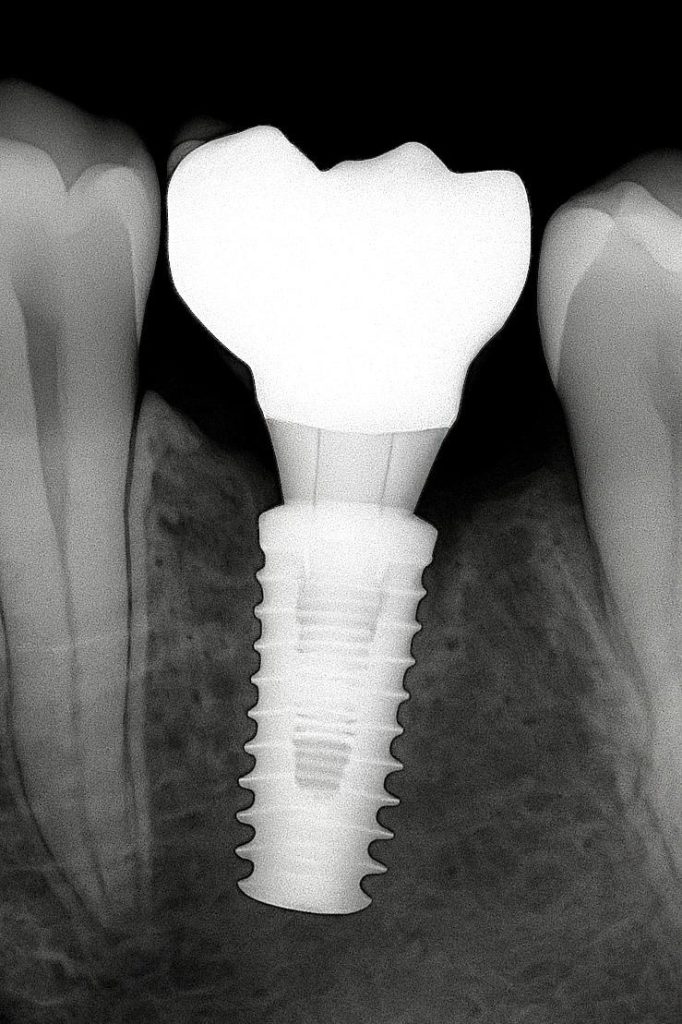

5. Post-Insertion Evaluation

Contacts and occlusion were refined to achieve even force distribution. Radiographic verification confirmed a passive fit and absence of any marginal discrepancies or bone loss.

SIX-MONTH FOLLOW-UP

- Peri-implant tissues: Firm and pink, with full papillary fill.

- Bone levels: Stable, with no radiolucency at the crestal margin.

- Restoration: Maintained gloss and anatomic form, free from wear or screw loosening.

The patient reported excellent comfort and function throughout the observation period.